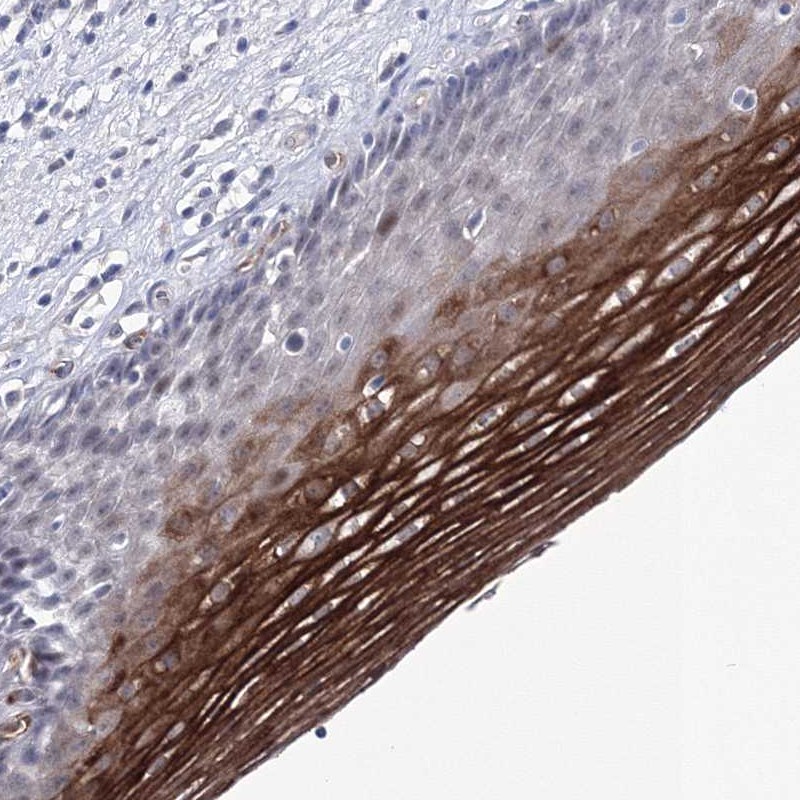

Immunohistochemical staining of human esophagus shows strong positivity in squamous epithelial cells.